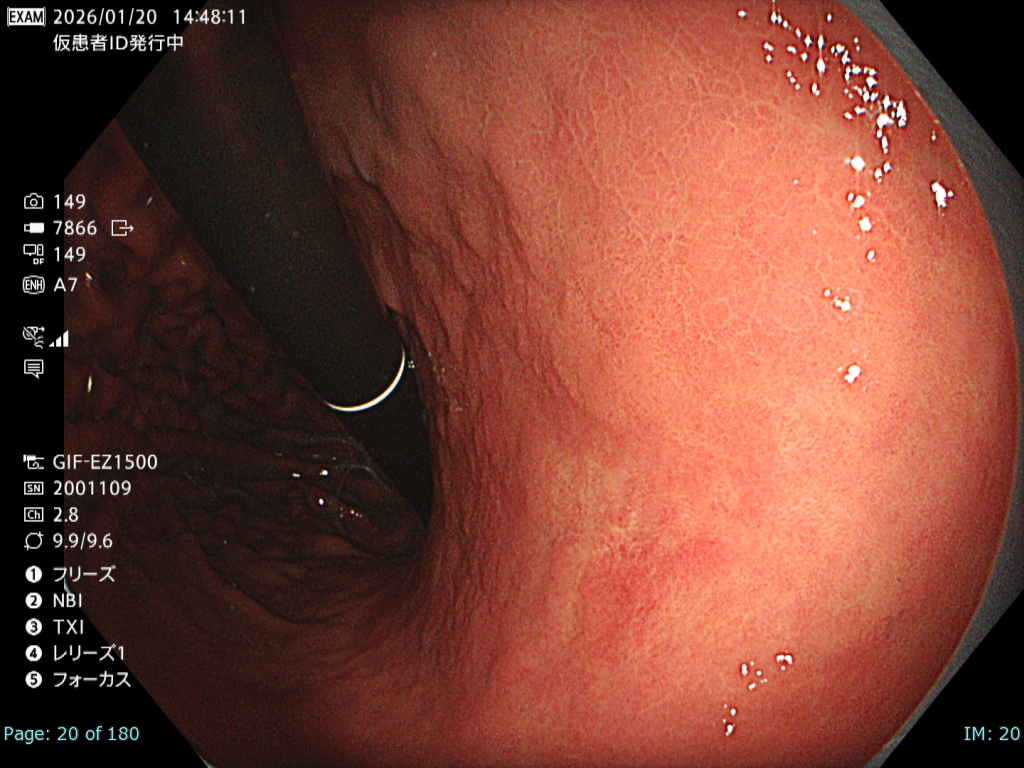

• 白色光観察①(近景)

強調設定:A7

図2

本病変は易出血性であり、血液洗浄後に観察・撮影できる時間は極めて短かったが、表面構造および色調を損なうことなく病変が明瞭に描出されている。記録画像として再評価にも十分耐え得る内視鏡画像である。

• 白色光観察②(中遠景)

図1

白色光非拡大観察では画面全体に良好なフォーカスが得られており、さらにBAI-MAC機能により深部まで十分な明るさが確保されている。そのため、2病変の性状および位置関係を正確に把握することが可能である。